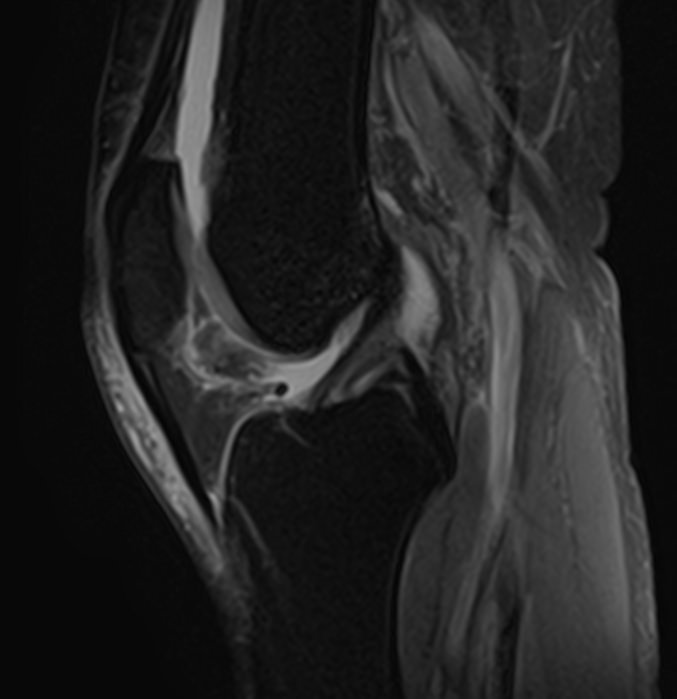

Магнитно-резонансная томография является современным высокоточным методом диагностики заболеваний опорно-двигательной системы человека. Во время исследования аппарат послойно сканирует анатомическую зону в различных плоскостях, затем с помощью компьютерных программ формирует трехмерные изображения с высокой точностью и достоверностью, что позволяет проводить эффективную диагностику заболеваний суставов.

Для выявления причин множественного поражения суставов в клинике «Доступная медицина» проводится комплексное обследование МРТ двух суставов, включающее два протокола исследования каждой анатомической области. При одностороннем поражении сустава также может назначаться МР сканирование одновременно двух симметричных сочленений для сравнения пораженной области со здоровым суставом на противоположной стороне. Это позволяет проводить более эффективную диагностику заболеваний суставов и назначать успешное лечение.

Какую патологию суставов можно выявить с помощью МРТ

• Из-за интенсивных нагрузок суставы часто подвержены травматизации (вывихи, подвывихи, внутрисуставные переломы, кровоизлияния в полости суставов – гемартрозы, растяжения, разрывы связок и сухожилий, ушибы мягких тканей),

• Воспалительные заболевания суставов (артриты, бурситы, синовиты, тендиниты, тендовагиниты).

• Дегенеративно-дистрофические заболевания суставов (артрозы, остеоартрозы).

• Врожденные аномалии развития (дисплазии, различные деформации и др).

• Выявление доброкачественных новообразований, например, кист и злокачественных опухолей (как первичных, так и метастазов).

• Обнаружение сосудистых заболеваний, поражений нервных волокон, патологии окружающих сустав мягких тканей.